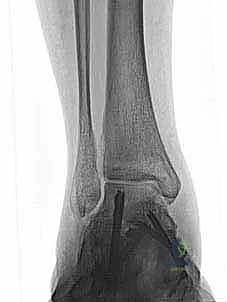

* الأشعة السينية أثناء الوقوف (Weight-bearing X-rays): ضرورية جداً لتقييم محاذاة العظام تحت تأثير وزن الجسم. يتم البحث عن اتساع في المسافة الصافية الإنسية (Medial Clear Space widening)، مما يدل على تمزق رباط الدالية العميق.

* الأشعة السينية مع الإجهاد (Stress Radiographs): يتم التقاط الصور أثناء تطبيق قوة معينة على الكاحل لإظهار عدم الاستقرار الخفي الذي لا يظهر في الصور العادية.